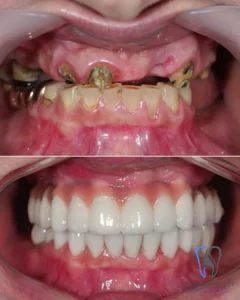

Case Study: 22 Zirconium Crowns

- Procedure: Hollywood Smile (22 Zirconium Crowns)

- Patient: Mosbah J. (from USA)

- Problem: Old, failing dental work and discoloration.

- Time: 6 Days in Istanbul